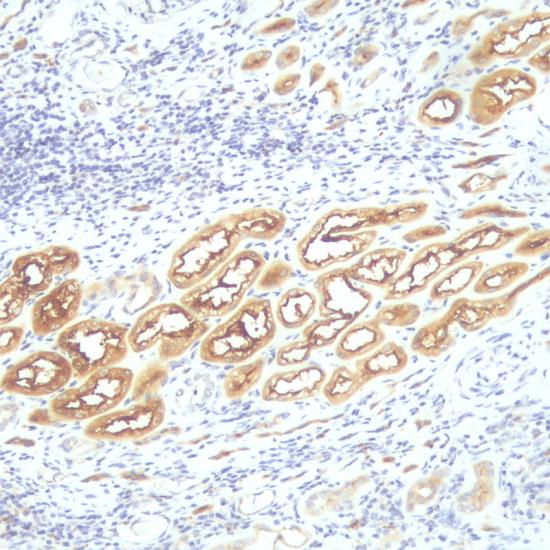

骨橋蛋白(Osteopontin)抗體試劑(免疫組織化學(xué)法) 閩廈械備20190291號(hào)

• 陽性部位:

細(xì)胞漿

• 陽性對照:

腎透明細(xì)胞癌

Osteopontin為一多功能蛋白質(zhì),參與骨骼的礦物質(zhì)化、細(xì)胞粘連、細(xì)胞遷移、慢性炎癥性疾病和細(xì)胞轉(zhuǎn)化,并參與腫瘤發(fā)生和轉(zhuǎn)移過程。它廣泛存在于正常成人組織和體液中。